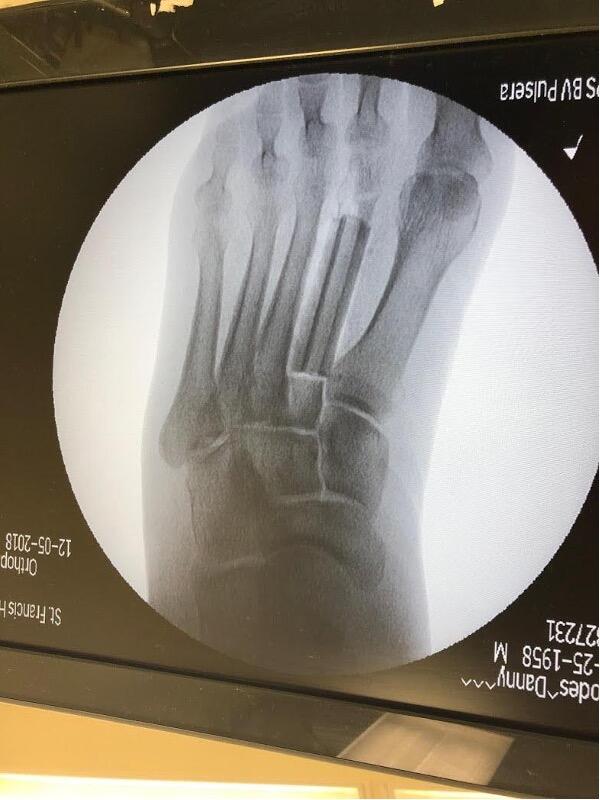

A 61-year-old male suffered multiple gunshot wounds, with one to the abdomen and the other to the left foot. The patient began IV antibiotics, as his injury was a Gustilo Anderson 3a open fracture to the left second metatarsal. We took the patient to the operating room for an emergent left foot incision and drainage with application of external fixation. We noted the second metatarsal shaft was shattered on fluoroscopy and inserted a mini rail external fixation into the preserved metatarsal head and base to preserve length.

After wound healing, we took the patient back to the operating room to remove the external fixator, place a fibular graft, and to perform open reduction and internal fixation (ORIF) of the second metatarsal. After removing the external fixator, we made a dorsal incision over the second metatarsal, exposing the bone. The second metatarsal was severely comminuted and angled. A sagittal saw then resected an approximately five cm section of the severe comminution and non-viable bone. We measured the deficit in the second metatarsal.